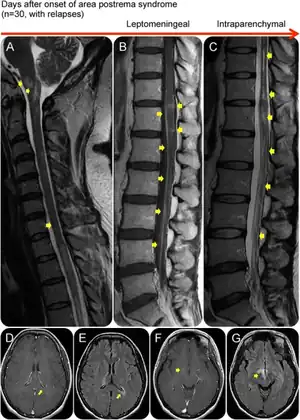

| An area postrema lesion in association with leptomeningeal enhancement and intraparenchymal BBB breakdownSpinal cord MRI (A–C) and brain MRI (D–G) from an AQP4-IgG–positive patient with NMOSD who presented with recurrent myelopathy of 1 month duration and area postrema lesion, which progressed into LETM. Images were obtained during acute attacks. An area postrema lesion (A) in association with subacute progression to LETM with leptomeningeal and intraparenchymal T1W contrast enhancement (arrows, B). The spinal cord lesions were also demonstrated on T2W and STIR images (C). Cerebral MRI during another attack with periependymal enhancement on T1W images at the lateral (D) and third ventricles (F). FLAIR images showing lesions along lateral ventricle (E), thalamus, and hypothalamus (G). (B) Used with permission of the publisher from Flanagan EP, Weinshenker BG. Neuromyelitis optica spectrum disorders. Curr Neurol Neurosci Rep 2014;14:483. Copyright © 2014, Springer Science+Business Media New York. AQP4-IgG = aquaporin-4 immunoglobulin G; BBB = blood-brain barrier; FLAIR = fluid-attenuated inversion recovery; LETM = longitudinally extensive transverse myelitis; NMOSD = neuromyelitis optica spectrum disorder; T1W = T1 weighted; T2W = T2 weighted. | |